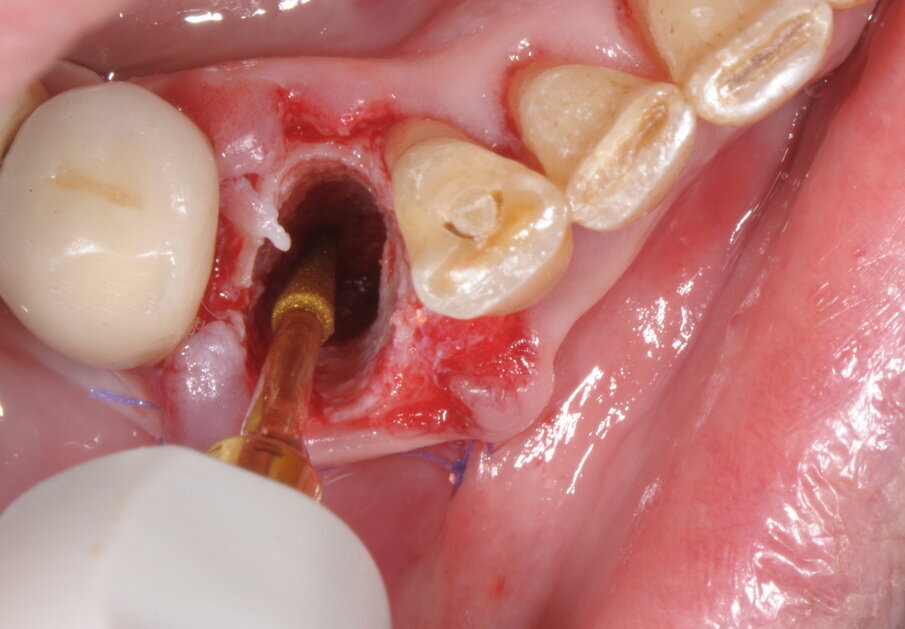

Questa separazione determina la creazione di uno spazio di manovra all’interno dell’alveolo che favorisce la lussazione, con leva manuale, della radice senza determinare compressioni a carico delle superfici alveolari, specie quella corticalizzata vestibolare, poco elastica e di scarso spessore (Figg. 4, 5; Vercellotti, 2016). Dopo accurata detersione dell’alveolo residuo integro, grazie all’effetto cavitazione della soluzione fisiologica, si è proceduto all’allestimento del sito implantare attraverso una tecnica di preparazione combinata che vede l’utilizzo sia di frese a spirale che inserti PIEZOSURGERY. In questo protocollo chirurgico di preparazione endo-alveolare del sito implantare gli inserti PIEZOSURGERY permettono con facilità la perforazione ossea e l’allestimento del sito seguendo un asse differente rispetto a quello dell’alveolo residuo, allo scopo di ricercare la maggiore stabilità primaria possibile dell’impianto (pur mantenendo un adeguato profilo di emergenza protesico).

Fig. 4

Fig. 5